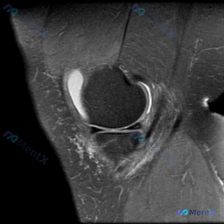

差点被带偏!本来找软骨异常,核心病灶居然在关节外

拿到这个膝关节MRI矢状位影像的时候,一开始给的提示是找软骨异常,差点就直接锚定在关节内病变了,整理一下完整的分析过程给大家参考。 先整理影像核心信息 1. 骨骼关节: 股骨髁皮质完整,没有骨折、骨质破坏,关节对合关系正常 2. 软骨: 股骨髁关节软骨可见条带状高信号,是本次提示的"软骨异常"所在...